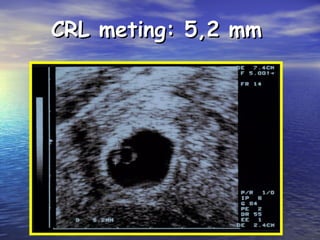

CRL meting: 5,2 mmCRL meting: 5,2 mm